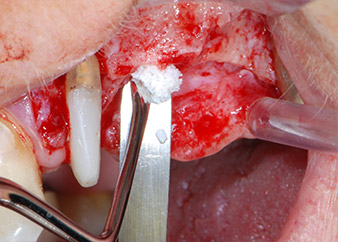

Zunächst wurde in einem Versuch, das Paro-Endo-Problem zu lösen, an der verbleibenden Wurzeloberfläche ein vorsichtiges Debridement mit einem piezochirurgischen Gerät vorgenommen (Piezomed, W&H) (Abb. 4); dann wurde der Apex mit dem gleichen Instrument im Sinne einer WSR abgetragen, um das verbleibende infizierte apikale Gewebe zu entfernen (Abb. 5). Eine retrograde Füllung war nicht notwendig, da die orthograde Füllung gerade revidiert worden war.

Brückenpfeiler

Abb. 4: Um den Zahn 24 als vorläufigen Brückenpfeiler zu erhalten, wird das Parodont mit einem piezochirurgischen Sytem gereinigt ...

bukkale Wurzelspitze

Abb. 5 ... und die bukkale Wurzelspitze mit dem gleichen Instrument abgetragen (WSR).